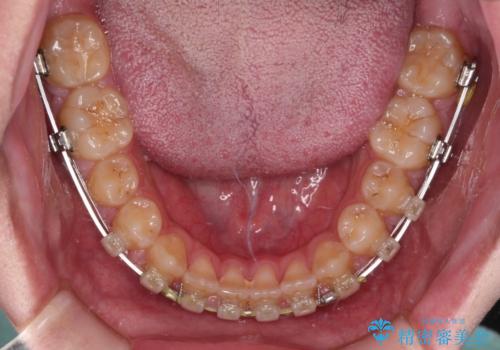

空隙歯列を閉じる 舌のトレーニングとワイヤー矯正

- 上下前歯の隙間を気にして来院された患者様です。

飲み込みや話をするときに舌を突出させる癖が強くあり、それが原因でスペースが空いていました。

舌癖を改善するためのトレーニングを行いながら、ワイヤー装置を用いて前歯の隙間を閉じていくこととしました。

舌の突出癖がなかなか改善されず、治療期間は当初予定よりも大分長くなりました。

装置除去を予定していた日に、油断されたのか1mmほどのスペースを作ってしまったため、除去が3ヶ月延長されたことで、舌のトレーニングの重要性を理解していただきました。

装置除去後もトレーニングを継続されているようで、後戻りによるスペースは今のところ認められておりません。